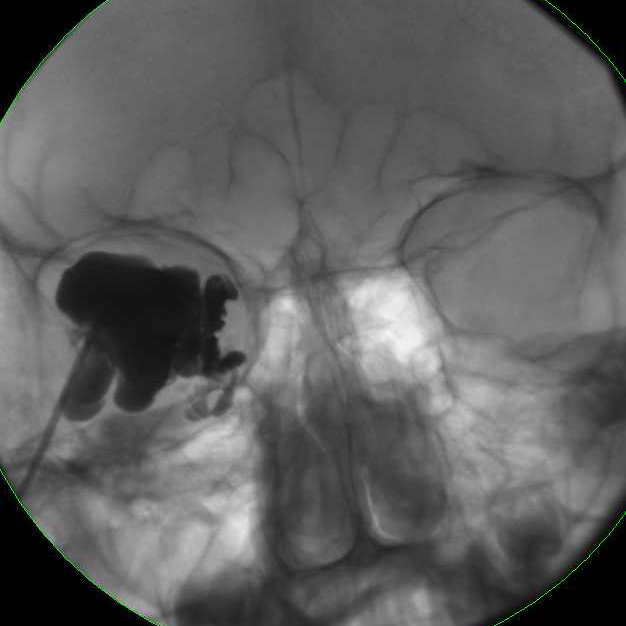

MRI of large LM cyst (top), catheter passing through lower lid (left), cystogram (right).

If treating a VM, as in treating a VM anywhere else in the body, a venogram under fluoroscopy is useful to assess the size of the lesion, the routes of venous drainage, and the rate of run off. Using standard fluoroscopic guided sclerosant injection techniques, the foams are all very well visualized especially under subtraction technique.